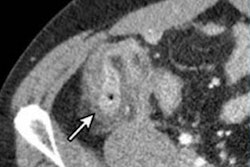

Contrast-enhanced standard-dose CT is typically used to diagnose acute appendicitis, but Haijanen's team sought to explore whether using less radiation would prove just as effective. The study included 856 patients (median age, 37), of whom 454 (53%) underwent low-dose CT and 402 (47%) underwent a standard dose exam for suspected appendicitis between April 2017 and November 2018.

The investigators found that the overall accuracy of low-dose CT for identifying patients with and without acute appendicitis was essentially the same as the accuracy of standard-dose CT, at 98% and 98.5%, respectively. The accuracy for distinguishing between uncomplicated and complicated appendicitis was 90.3% for low-dose CT and 87.6% for standard dose. Mean radiation dose for the low-dose exams was 3 mSv, compared with 7 mSv for the standard dose exams.

The study findings demonstrate that CT radiation dose can be significantly decreased without negative effect on diagnostic accuracy, said lead author Dr. Paulina Salminen of the University of Turku in a statement released by the journal.